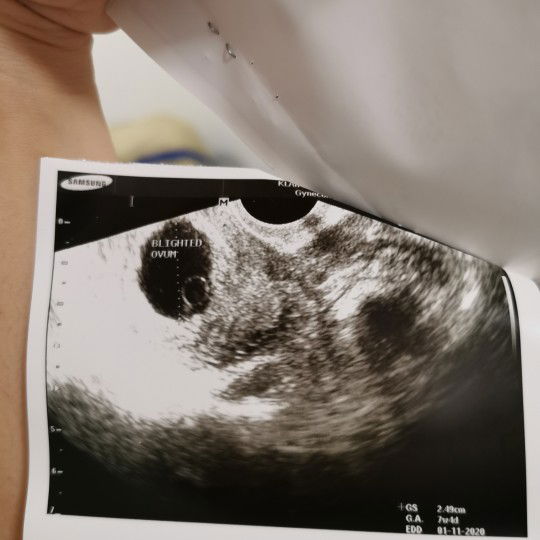

ช่วยดูหน่อยคะ

เป็นคนรอบเดือนไม่ตรงเลย​ 32+ ถ้านับประจำเดือนล่าสุด​ ได้8w4d ถุงขนาด​ 2.49 หมอบอกให้ดูดออก​ ควรรออีกหน่อยไหมคะ​ เป็นไปได้ไหมว่าไข่ตกช้า​ มีใครเป็นแบบนี้ไหมค่ะ​ อธิบายทีคะ